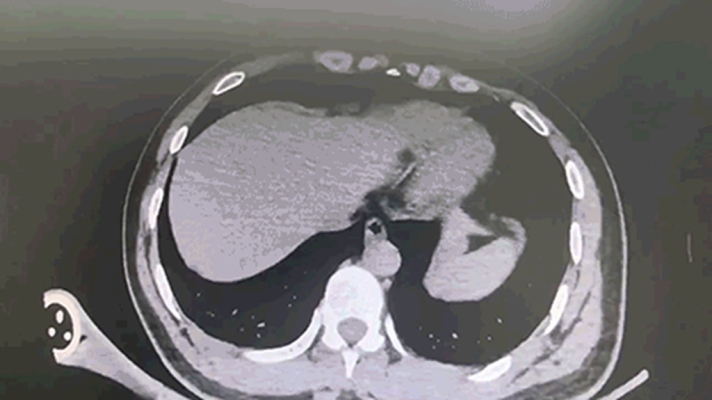

早高峰车祸重伤 西安国际医学中心医院多学科接力上演生死时速